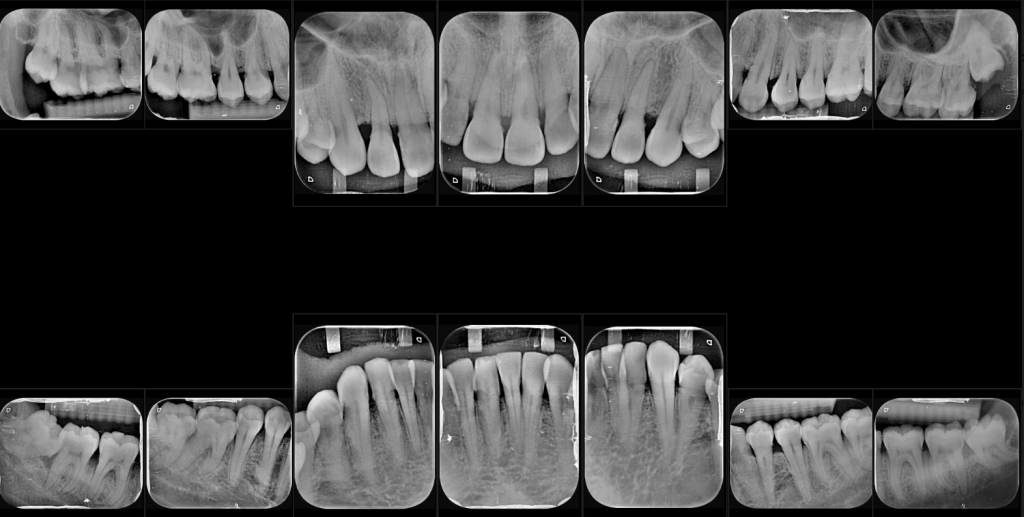

Aunque alguna dentista me había advertido que tenía que operarme tarde o temprano, por suerte nunca tuve mayor problema. Fue hace unos meses que acudí a otra cita odontológica que se me reveló otro asunto, con las encías, que culminó en que debía de retirarme las muelas del juicio sí o sí. Pero como todo eso me resultaba carísimo con esa dentista particular, me fui a la UNAM, a la facultad de odontología, con la finalidad de ahorrarme unos diez mil pesos (que sí ahorré).

La verdad es que fue una muy buena decisión: me atendieron, al menos, tres dentistas distintos, cada uno especialista en lo suyo. Me hicieron limpieza profunda, eliminaron caries, corrigieron mi cepillado, etcétera, etcétera, con la finalidad de llegar al tiro a una cirugía en la que un maxilofacial (de lo más profesional, aunque con el colmo de los dentistas: fea sonrisa y mal aliento) se tardó una hora. Este dijo que eran más los pros que los contras. Entre los pros: que una de las muelas impactadas (es decir: acostada, horizontal, recargada sobre otra) no aniquilara a la que tenía a su lado, provocando que me sacaran las dos.

Si bien la anestesia hizo lo suyo, el sonido fue el terror. La forma en que trituran, parten, jalan, mueven, cortan y extraen las muelas le hacen a uno imaginarse cosas que, de algún modo, se materializan cuando, al terminar, un bonche de muelas (parecieran diez, no cuatro) yacen sangrantes sobre un límpido papel azul.